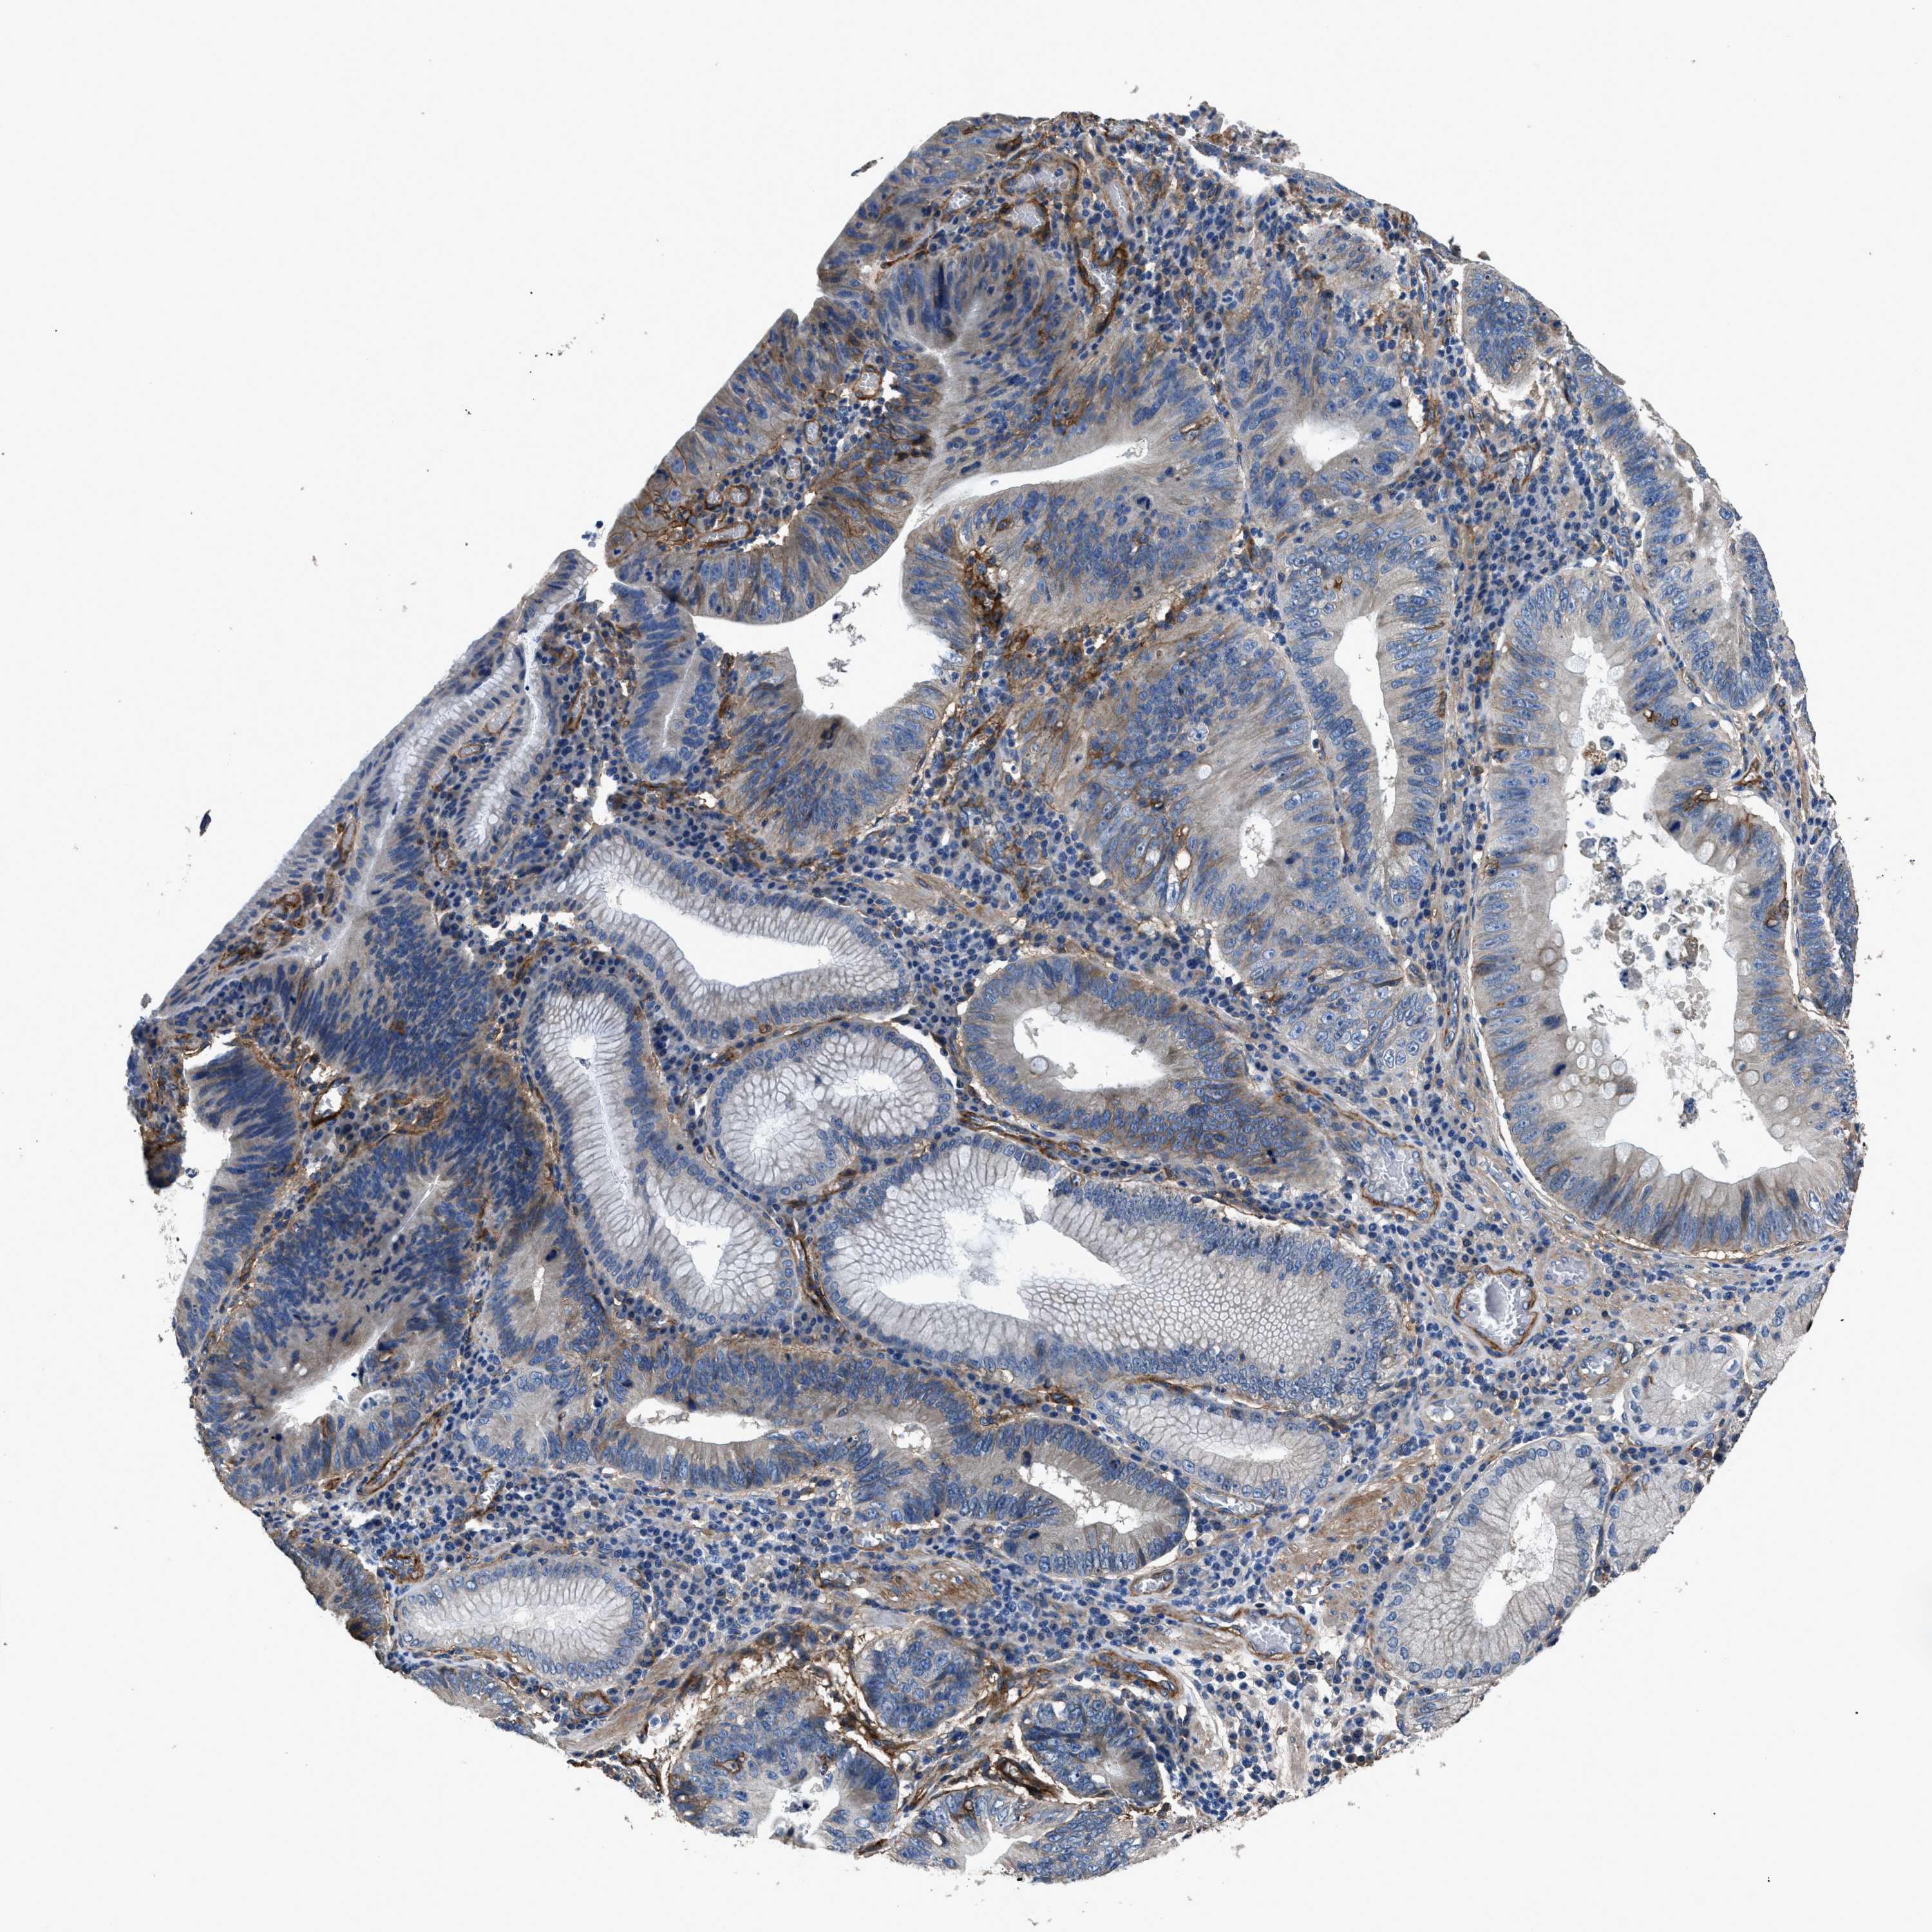

STOMACH CANCER - Protein expressioni

A mouse-over function shows sample information and annotation data. Click on an image to view it in a full screen mode. Samples can be filtered based on level of antibody staining by selecting one or several of the following categories: high, medium, low and not detected. The assay and annotation is described here.

Antibody stainingi

Antibody staining in the annotated cell types in the current human tissue is reported as not detected, low, medium, or high, based on conventional immunohistochemistry profiling in selected tissues. This score is based on the combination of the staining intensity and fraction of stained cells.

Each image is clickable and will lead to virtual microscopy that enables deeper exploration of all samples and also displays staining intensity scores, fraction scores and subcellular localization as well as patient and tissue information for each sample.

Antibody HPA009285

Antibody HPA017139

Antibody CAB017826

Staining

High

Medium

Low

Not detected

Intensity

Strong

Moderate

Weak

Negative

Quantity

>75%

75%-25%

<25%

None

Location

Nuclear

Cytoplasmic/membranous

Cytoplasmic/membranous,nuclear

Adenocarcinoma, NOS

Adenocarcinoma, High grade